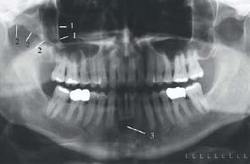

The image on the left reveals the ghost image of the cervical vertebrae (1) as a diffuse radiopacity in the midline of the film, which should not be confused with osteoblastic abnormalities. These ghosts can be minimized by ensuring the patient’s neck is straightened vertically. Ghost images of earrings (2) are identified in the areas of the orbits, and should be recognized because the true images of the earrings (3) are visible at the edges of the film. Similarly, the intense, blurred radiopacities near the angles of the mandible represent ghost images of lead markers (4, 5) in the vertical head positioning device. Note that the ghosts of the “L” (4) and “R” (5) are on the contralateral sides and are superior to the true images.